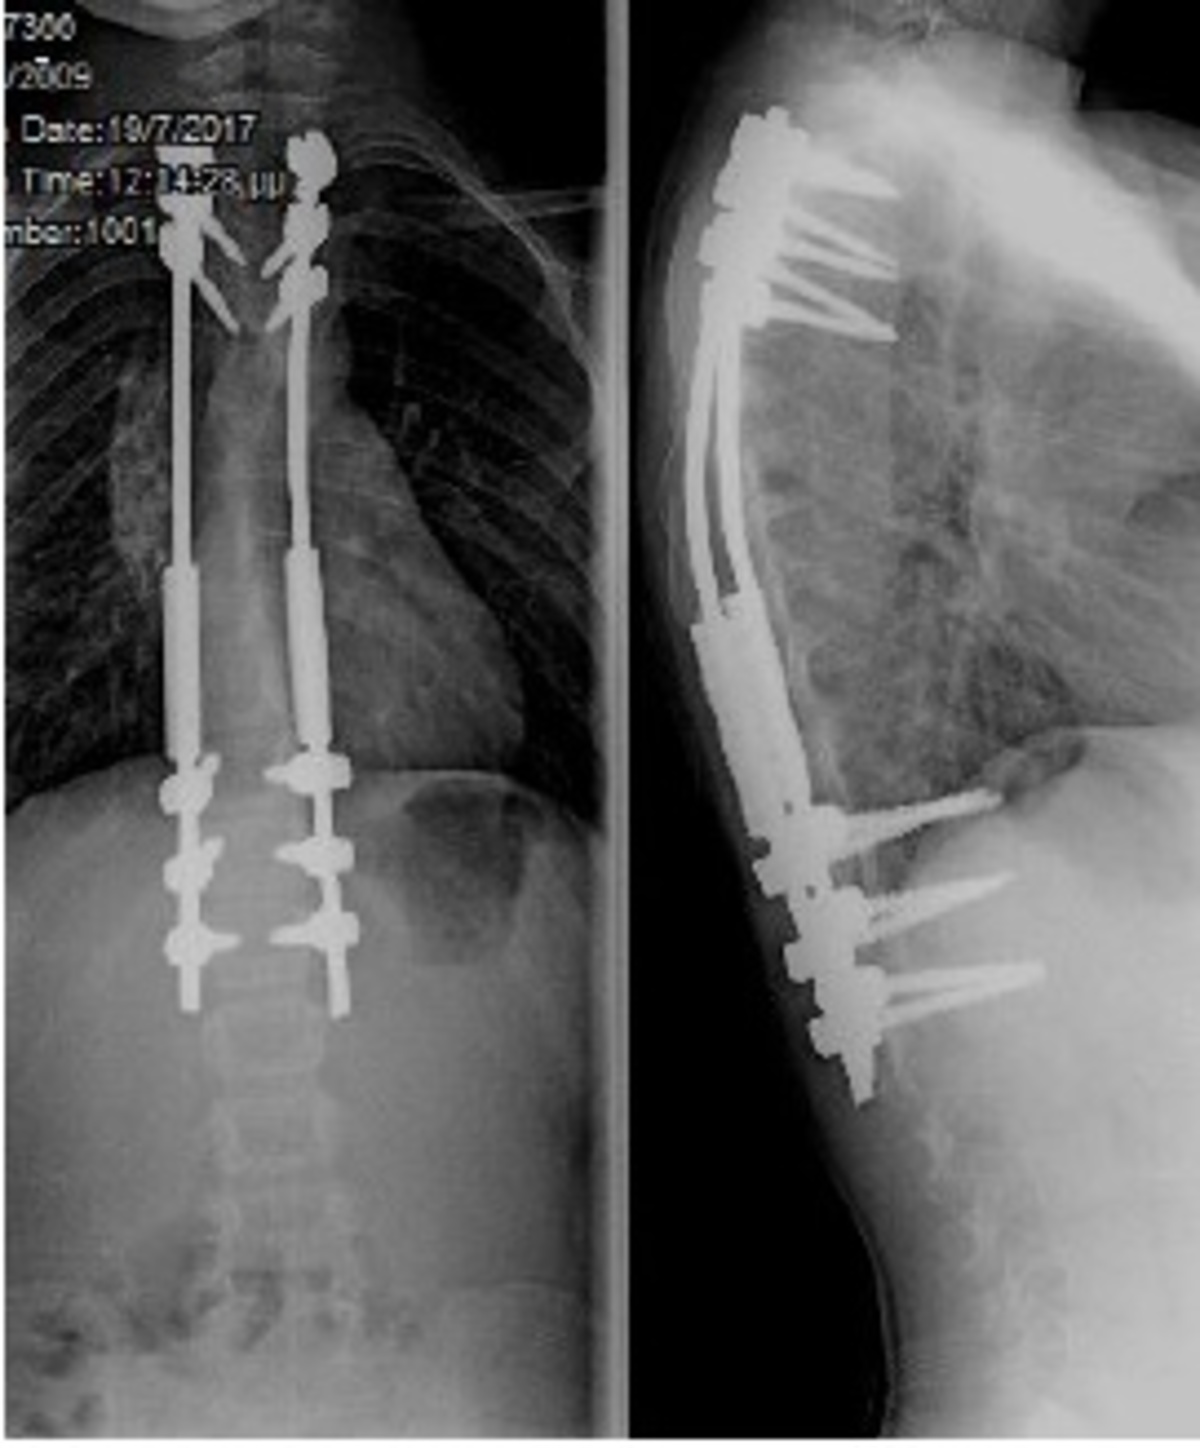

Σύνθετες παραμορφώσεις της σπονδυλικής στήλης, όπως είναι η σκολίωση και η κύφωση, ακόμη και σε περιπτώσεις παιδιών με συγγενείς ανωμαλίες ή νευρομυϊκές παθήσεις, αντιμετωπίζονται χειρουργικά και στις νεαρότερες ηλικίες. Τα σύγχρονα συστήματα σπονδυλοδεσίας επιτρέπουν τη διόρθωση της παραμόρφωσης, με παράλληλη επιμήκυνση της σπονδυλικής στήλης, ενώ το παιδί συνεχίζει να αναπτύσσεται και να ψηλώνει. Αποτέλεσμα είναι τα παιδιά – αλλά και οι οικογένειές τους – να αντιμετωπίζουν με ασφάλεια και να αφήνουν οριστικά πίσω τους ένα δύσκολο πρόβλημα, όπως είναι μια παραμόρφωση της σπονδυλικής στήλης, συνεχίζοντας με μια φυσιολογική ανάπτυξη και ακολουθώντας όλες τις δραστηριότητες των παιδιών της ηλικίας τους.

Η αντιμετώπιση των παραμορφώσεων της σπονδυλικής στήλης των ενηλίκων, ένα πολύ ιδιαίτερο και δύσκολο χειρουργικό πρόβλημα, βασίζεται πλέον στον ακριβή γεωμετρικό τρισδιάστατο προεγχειρητικό σχεδιασμό, με τη βοήθεια υπολογιστικών προγραμμάτων χειρουργικού σχεδιασμού. Με την τεχνική αυτή, σχεδιάζεται με απόλυτη ακρίβεια η χειρουργική επέμβαση, ενώ προκατασκευάζονται και υπάρχουν διαθέσιμα στο χειρουργείο εξατομικευμένα, για τον κάθε διαφορετικό ασθενή, υλικά σπονδυλοδεσίας.

Επιπλέον, με την χρήση της διεγχειρητικής τρισδιάστατης νευροπλοήγησης (ρομποτική χειρουργική της σπονδυλική στήλης), είναι εφικτή η ταχύτατη, με ακρίβεια και ασφάλεια, εμφύτευση των υλικών οστεοσύνθεσης και η πραγματοποίηση ακόμη και των πιο λεπτών χειρουργικών επεμβάσεων, σε όλες τις περιοχές της σπονδυλικής στήλης, από τον αυχένα έως και το ιερό οστό. Η διόρθωση της παραμόρφωσης ελέγχεται διεγχειρητικά και ο χειρουργός έχει τη δυνατότητα επιπλέον τροποποιήσεων την ώρα του χειρουργείου, ώστε να πετύχει το καλύτερο δυνατό αποτέλεσμα.